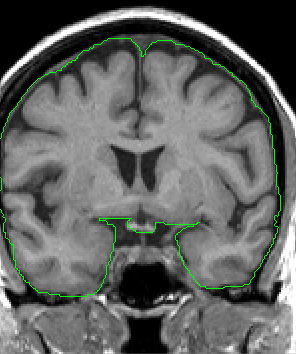

Excluded from ICC: skull,

subcutaneous and orbital fat, mastoid and nasal sinuses, dural venous

sinuses, larger blood vessles beyond the surface of the brain, bony

protuberances (i.e., dorsum sellae), and cranial nerve roots, since

they extend beyond the surface of the brain.

In the anterior portion of the ICC, using either the outline provided by the automation or a contour you generate, extract outlines that include all visible Cortex as well as all surrounding CSF. Draw a line to divide the ICC into left and right hemispheres and then extract each side separetely.

Take care to exclude all dura mater and sinuses.

Moving posteriorly, take care to exclude the Superior Sagittal Sinus, as it is often included by the automation.

In the middle portion of the ICC, continue extracting all Cortex and CSF, but be aware of and exclude all veins, cranial nerve roots, and bony protuberances that appear, particularly as the brainstem appears.